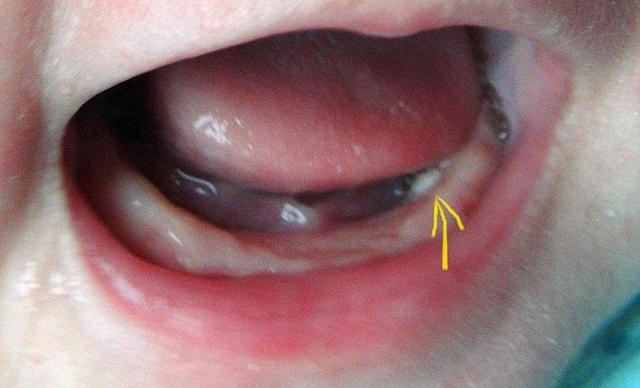

5.还有时候,当宝宝乳牙自行发育,牙板破碎之时,那些破碎的牙板也是个引子,也就是其中没被吸收的碎物,它会慢慢增生,在宝宝尚鲜嫩的牙床上,长出白色小球状样的东西,也就是“马牙”了。